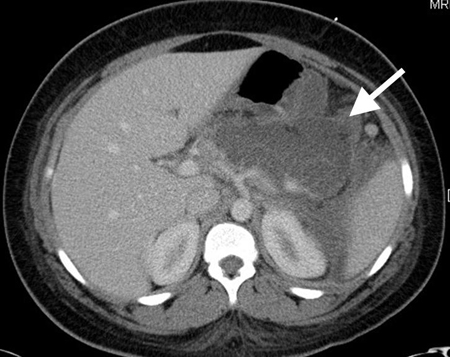

Tomografia computadorizada (TC) revelando fecalito (seta branca) fora do lúmen do apêndice consistente com apêndice perfurado

Do acervo de Dr. KuoJen Tsao; usado com permissão